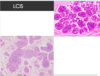

What is this?

Atypical lobular hyperplasia- consists of cells identical to those of lobular carcinoma in situ, but the cells do not fill or distend more than 50% of the acini within a lobule.

Surgeons typically do not surgically excise these cells